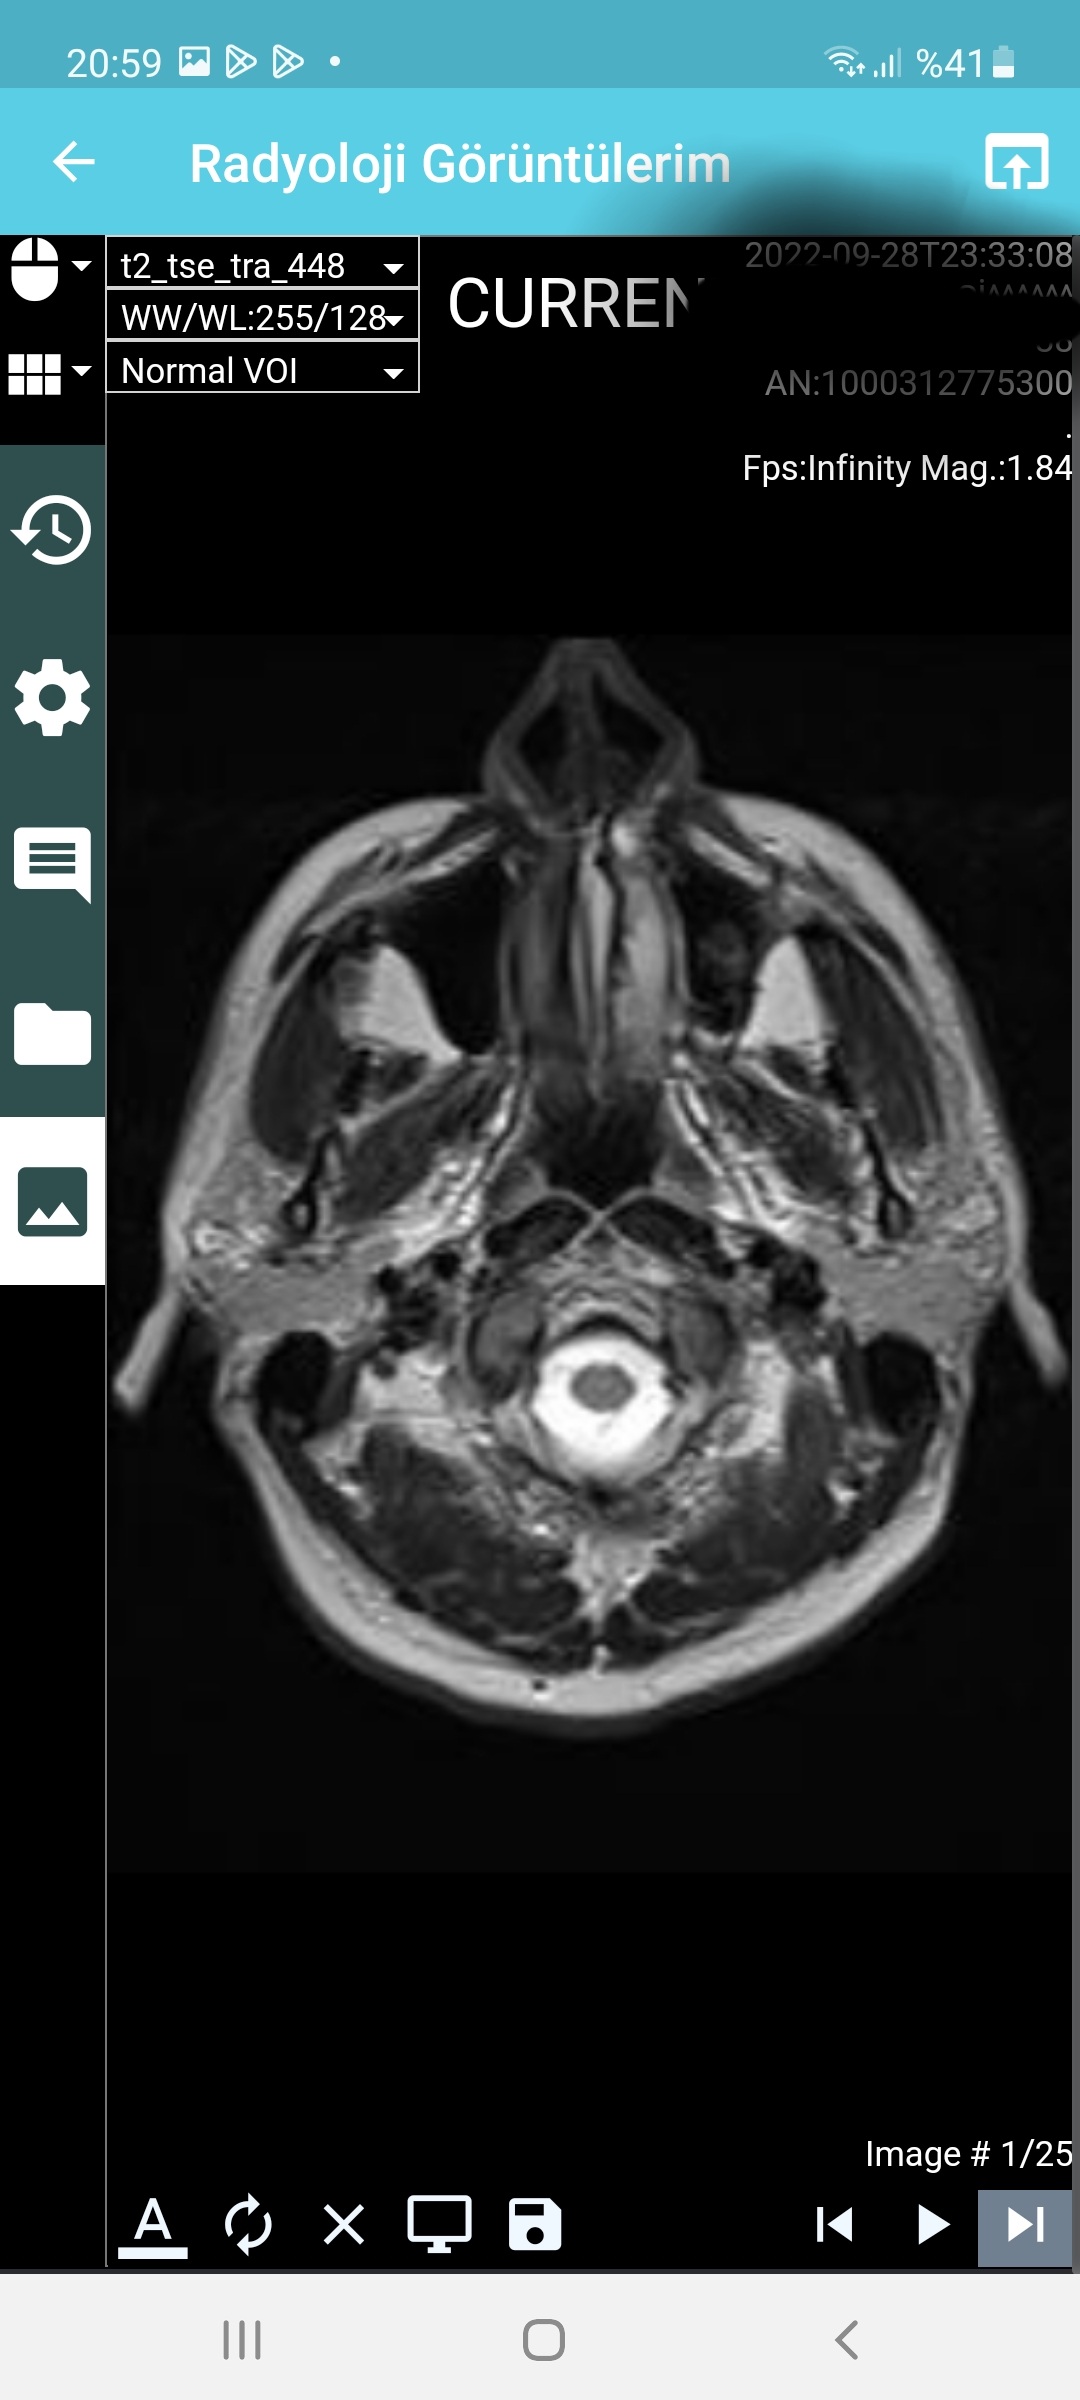

Arkadaşlar aranızda beyin emarı çektiren var mı yada bu konulardan anlayan ? Az önce emardan çıktım, emara sokan teknisyen pantolu ve kemerimi çıkartmadan emara soktu beni. Eee hani metal eşya ile girmek sakıncalı ve yasak degilmiydi? Şuan beynim şişmiş gibi acayip ağırlık var beynimde . Umarım bu emar sağlığa zararlı değildir. Radyasyon olmadığı için zararsız diyorlar ,umarım doğrudur. Hadi bunu geçtim ama o kemer umarım emar sonuçlarını etkilemez. < Bu mesaj bu kişi tarafından değiştirildi berlin007 -- 28 Eylül 2022; 23:49:8 > < Bu ileti mobil sürüm kullanılarak atıldı > |